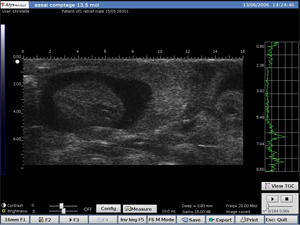

Le DERMCUP est équipé d’une sonde 25 MHz.

Il permet d’acquérir, de façon non-invasive, des coupes verticales in vivo: 16 mm x 12 mm.

• Détection précoce de tumeurs

• Suivi de l’évolution des tumeurs

Rein